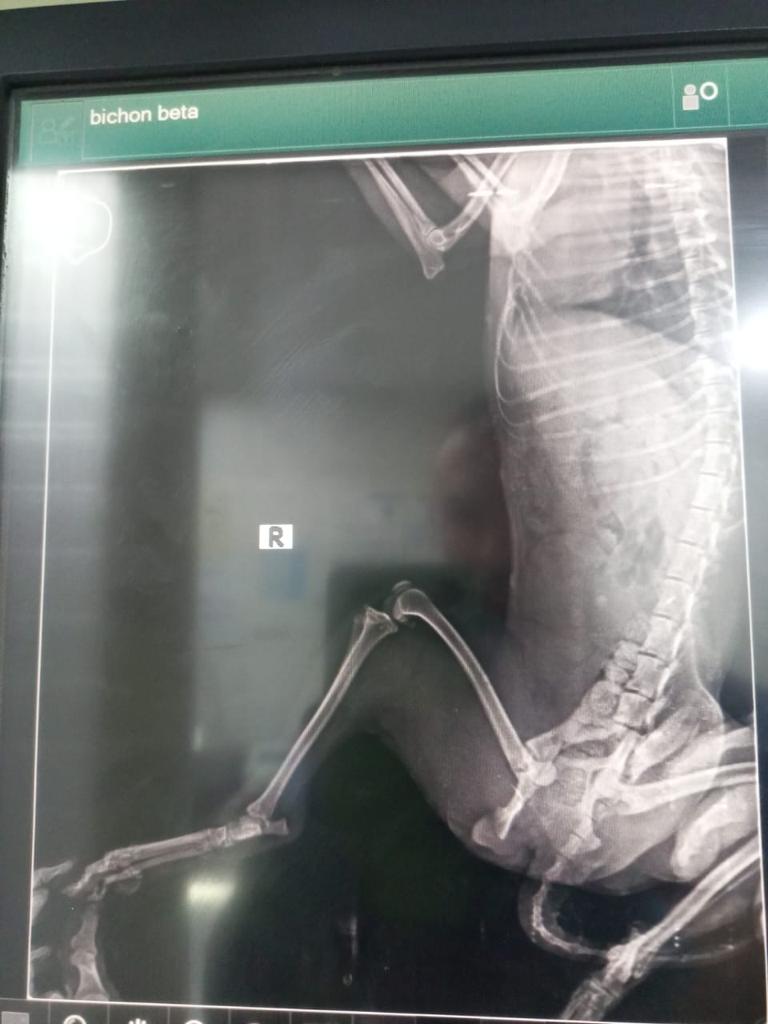

QUESA était utilisée pour la reproduction (d’après les témoignages) et laissée à la rue après avoir été blessée par un accident de la route (fémur cassé). Une enquête a permis de retrouver le « propriétaire » qui a refusé de la récupérer disant qu’elle ne lui servait plus à rien et qu’il ne comptait pas dépenser un centime pour elle.

Elle aura besoin d’un entretien des yeux réguliers (nettoyage/hydratation) et elle gardera une légère boiterie à la suite de son accident.